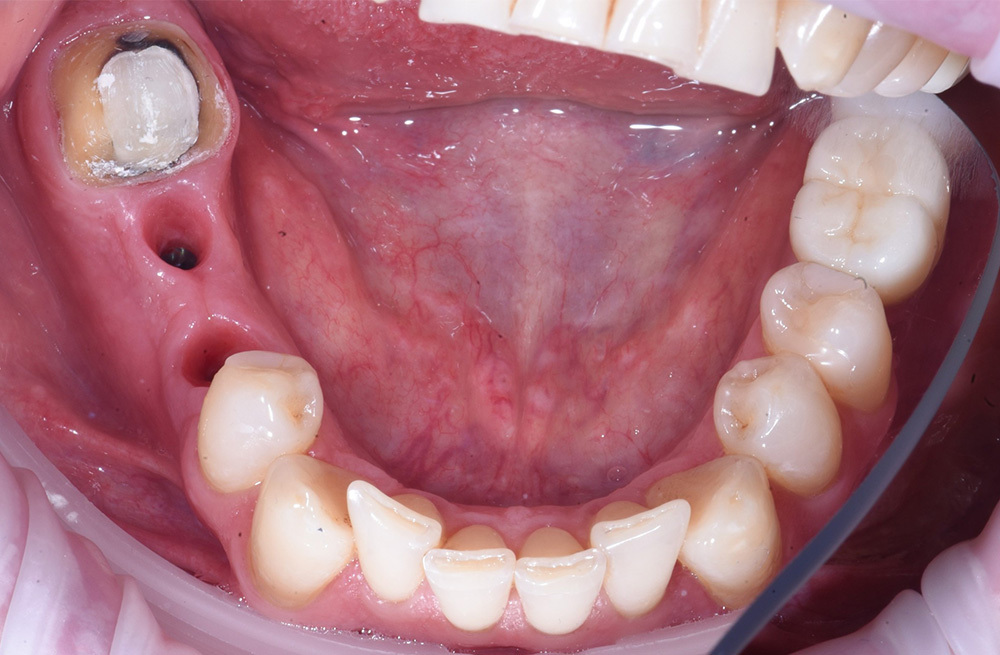

Тотальная реабилитация пациента с ятрогенными поражениями корней по схеме 6 на 6 и надёжной балочной конструкции